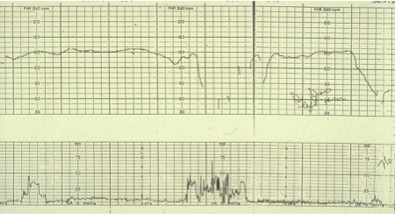

Fig 1) This fetal heart rate tracing on the right side shows a deep variable deceleration. The beat to beat variability is normal.

Fig 2) This later tracing shows 2 long deep variable decelerations, and loss of normal beat-to-beat variability.

Fig 3) This even later tracing shows progressive bradycardia.